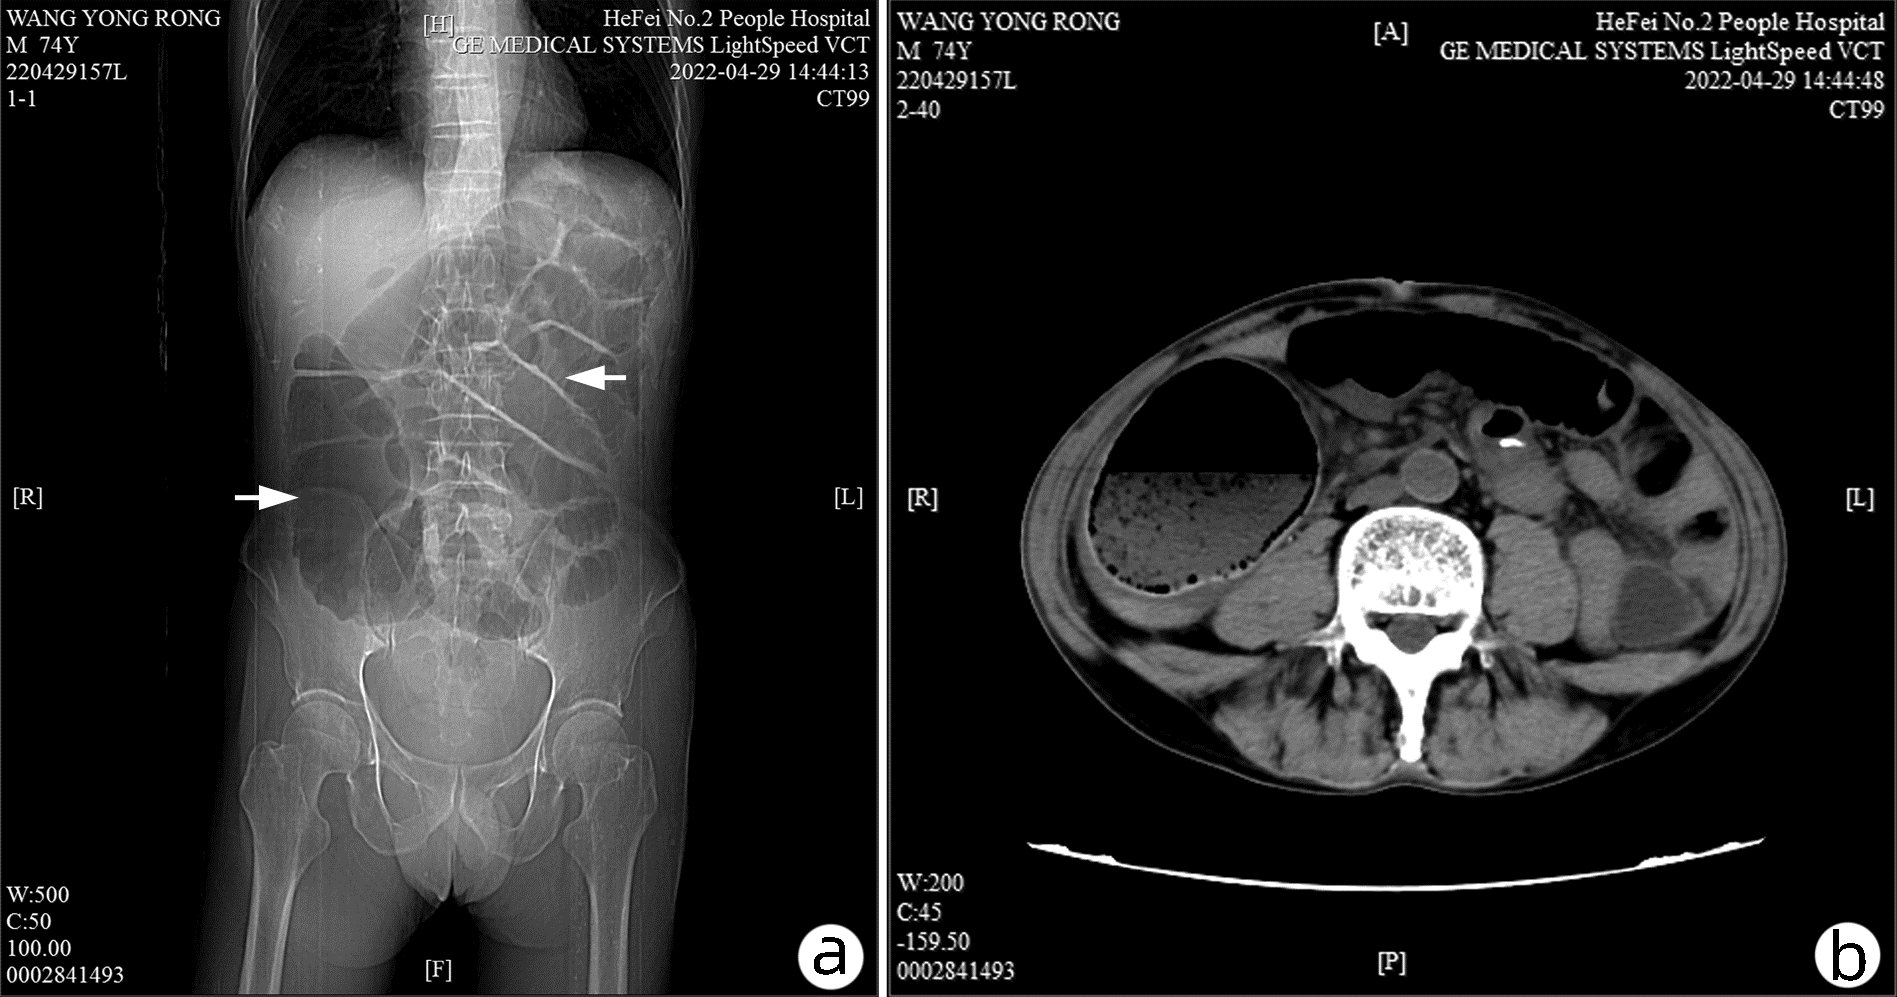

Cholecystoduodenal fistula with gallstone ileus accompanied by colon cancer: A case report